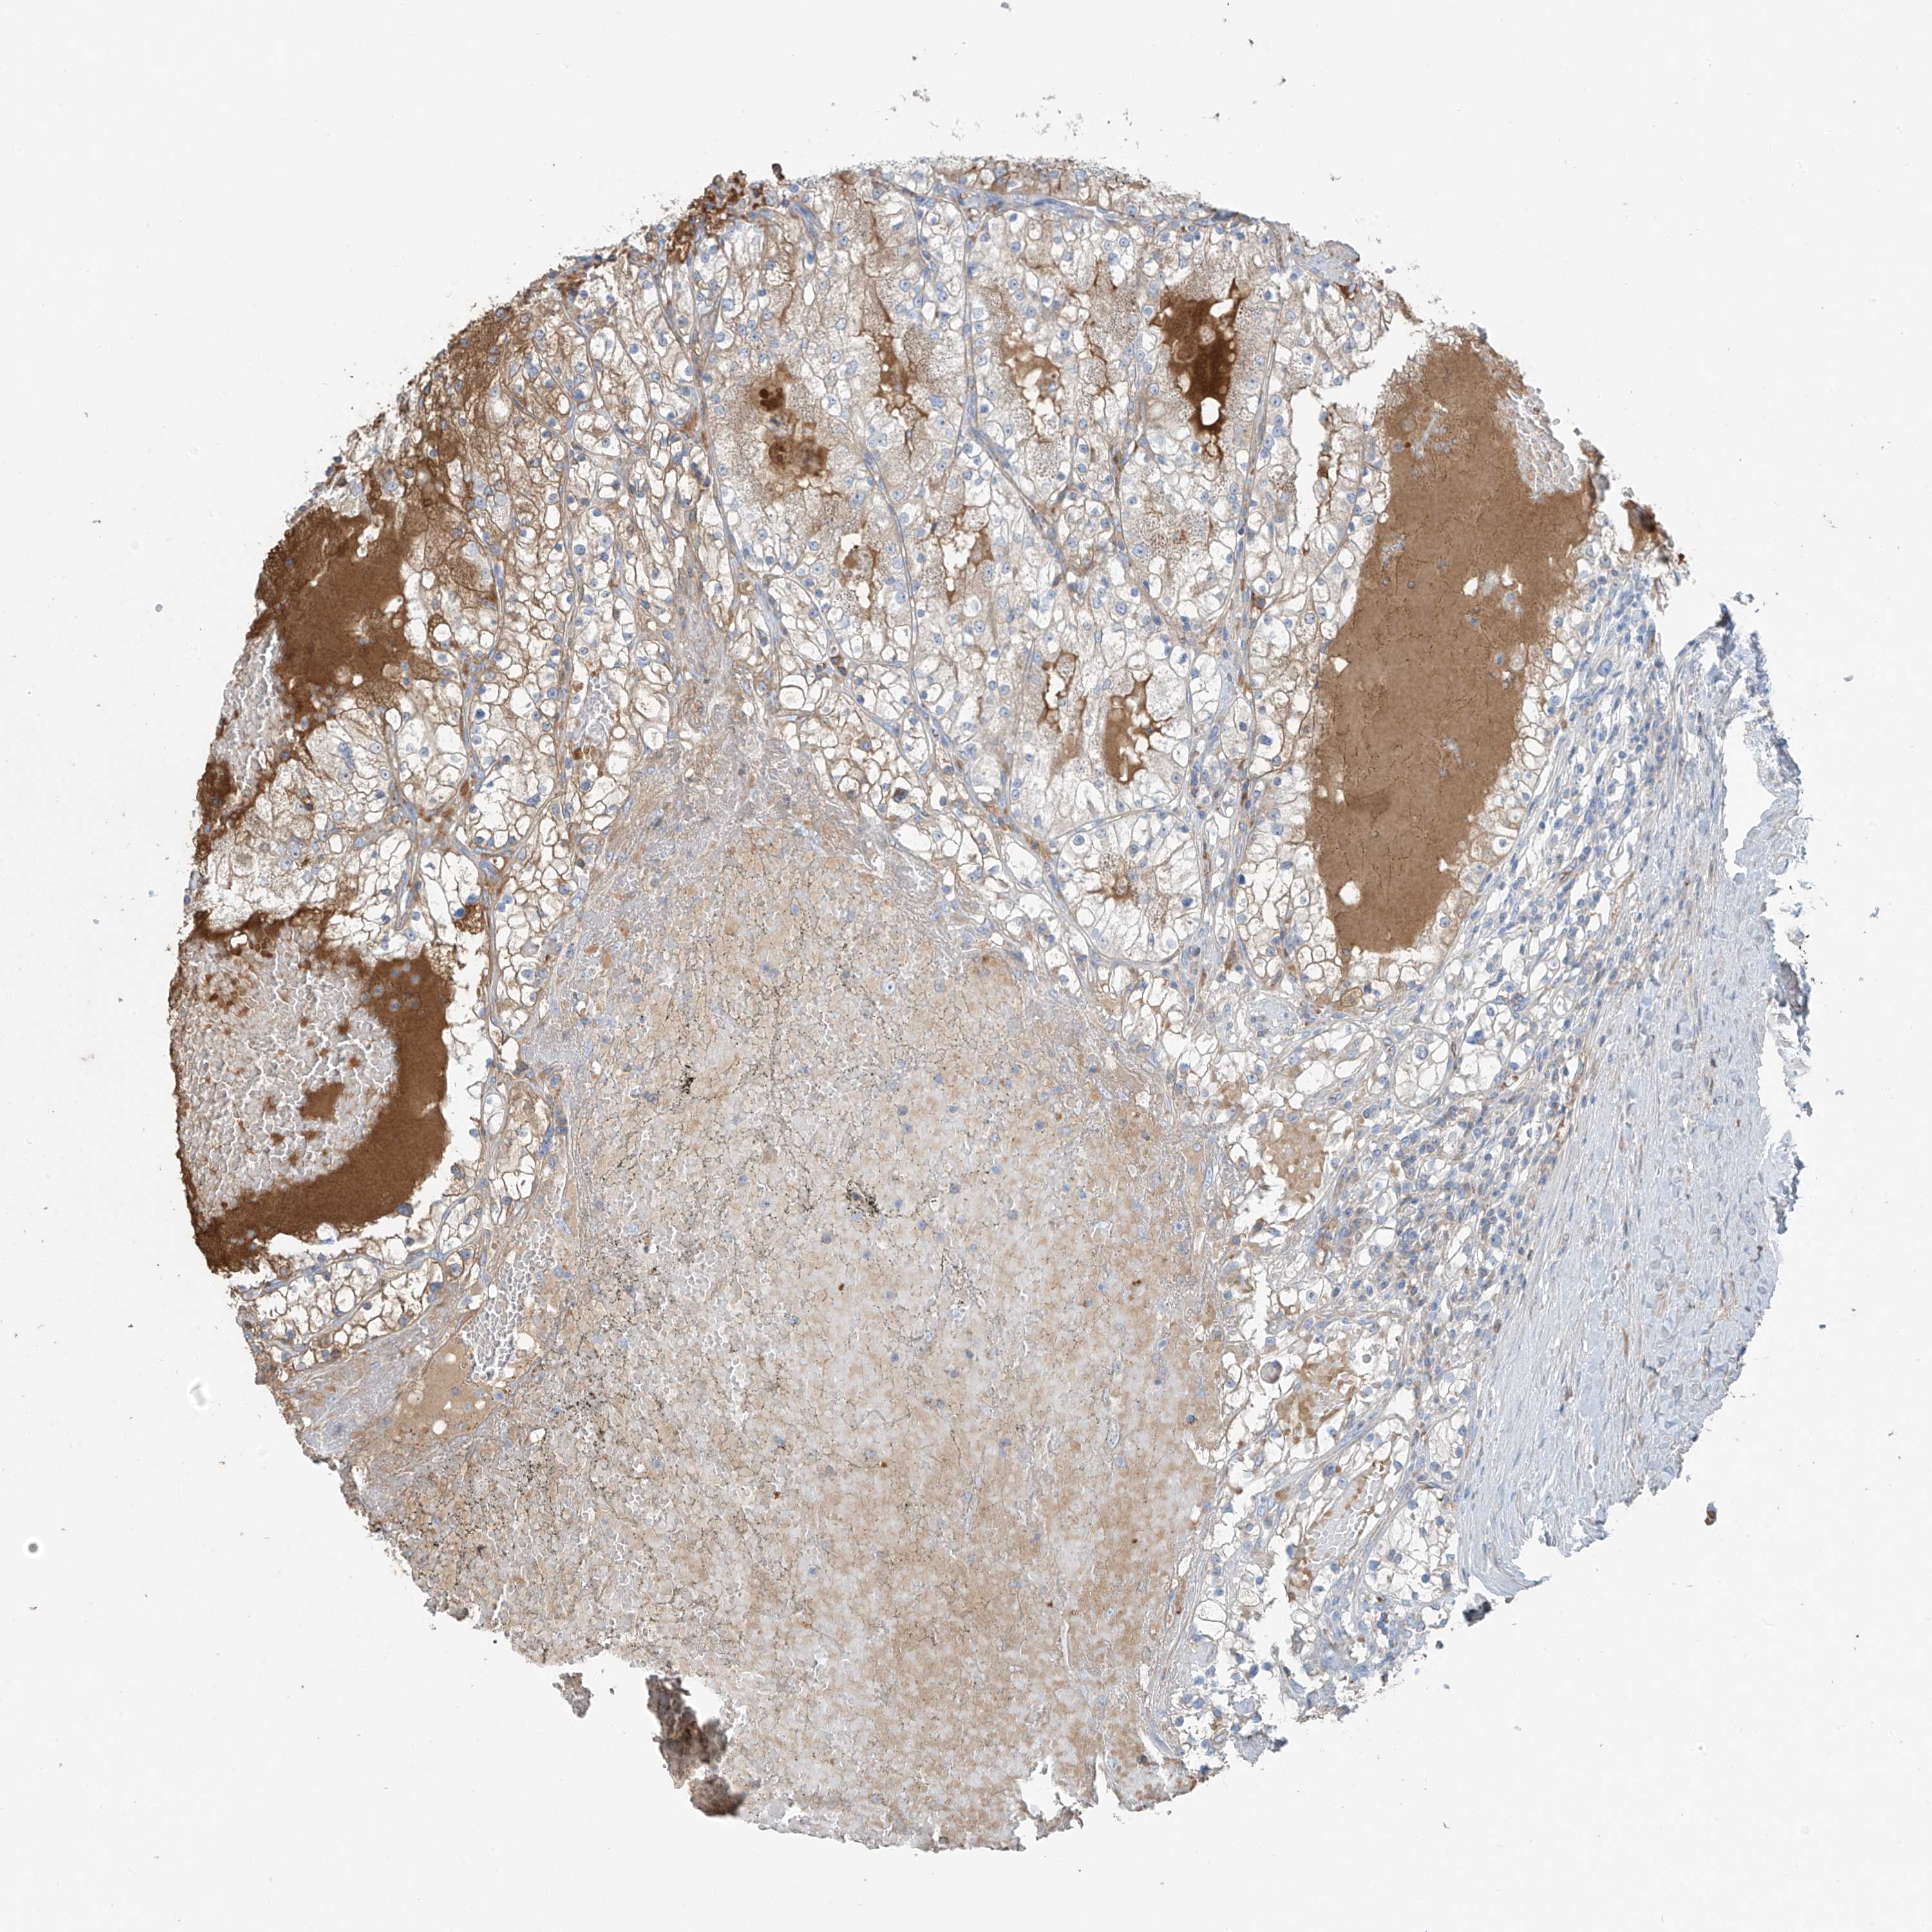

KIDNEY RENAL CLEAR CELL CARCINOMA (VALIDATION) - Interactive survival scatter ploti

The Survival Scatter plot shows the clinical status (i.e. dead or alive) for all individuals in the patient cohort, based on the same data that underlies the corresponding Kaplan-Meier plots. Patients that are alive at last time for follow-up are shown in blue and patients who have died during the study are shown in red.

The x-axis shows the expression levels (FPKM) of the investigated gene in the tumor tissue at the time of diagnosis. The y-axis shows the follow-up time after diagnosis (years). Both axes are complimented with kernel density curves demonstrating the data density over the axes. The top density plot shows the expression levels (FPKM) distribution among dead (red) and alive patients (blue). The right density plot shows the data density of the survived years of dead patients with high and low expression levels respectively, stratified using the cutoff indicated by the vertical dashed line through the Survival Scatter plot. This cutoff is automatically defined based on the FPKM cutoff that minimizes the p-score. The cutoff can be changed by dragging the vertical line or by entering a cutoff value in the square labeled "Current cut-off".

Under the Survival Scatter plot the p-score landscape (black curve; left axis) is shown together with dead median separation (red curve; right axis). Dead median separation is the difference in median mRNA expression between patients who have died with high and low expression, respectively. It is calculated as follows: median FPKM expression of dead patients with high expression - median FPKM expression of dead patients with low expression. This is intended to aid the user in visually exploring custom cutoffs and the associated p-scores and dead median separation.

Individual patient data is displayed and can be filtered by clicking on one or more of the category buttons on the top of the page. Categories describing expression level and patient information include: high, low, alive, dead, female, male and tumor stages. The scale of the x-axis can be toggled between linear and log-scale by clicking on the "x log" button. Mouse-over function shows TCGA ID, patient information and mRNA expression (FPKM) for each patient.

& Survival analysisi

Kaplan-Meier plots summarize results from analysis of correlation between mRNA expression level and patient survival. Patients were divided based on level of expression into one of the two groups "low" (under cut off) or "high" (over cut off). X-axis shows time for survival (years) and y-axis shows the probability of survival, where 1.0 corresponds to 100 percent.

PDGFC is validated prognostic, high expression is favorable in Kidney Renal Clear Cell Carcinoma (validation)

: 6.46

Average pTPM 7.6

Number of samples 100